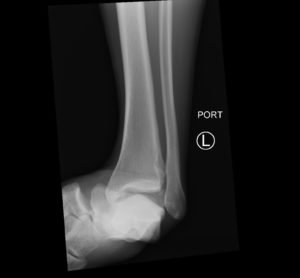

Subtalar dislocation is an unusual form of joint injury from high-energy trauma or athletic injuries. This case report describes a 22-year-old male who presented to the emergency department with left ankle pain after falling from his bicycle. Examination revealed significant deformity of the left foot and ankle. The foot pointed medially, and the bottom portions of the tibia and fibula were visible with the overlying skin intact. Radiographs confirmed left medial subtalar dislocation. There was no neurovascular compromise of the foot. The dislocation was successfully reduced under procedural sedation and the patient’s left leg was placed in a splint. He underwent post-reduction imaging and was instructed to remain non-weight-bearing and to follow up with orthopedics to discuss further management. The purpose of this report is to describe a case of a closed, medial subtalar dislocation and the approach to management.